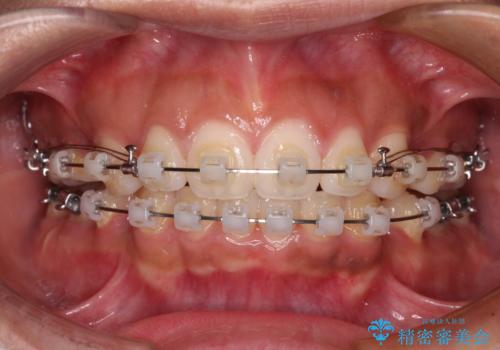

- クリアブラケット

- 出っ歯と口の閉じにくさ、デコボコを気にして来院された患者様です。

口元の突出感を改善するため、上下左右第一小臼歯4本の抜歯を行い、ワイヤー装置による矯正治療を行うこととしました。

舌の突出癖により上下前歯は非接触であり、非常に前方に飛び出している状態でした。

舌のトレーニングをしっかりと行っていただき、口の閉じやすい歯並びに仕上げることができました。